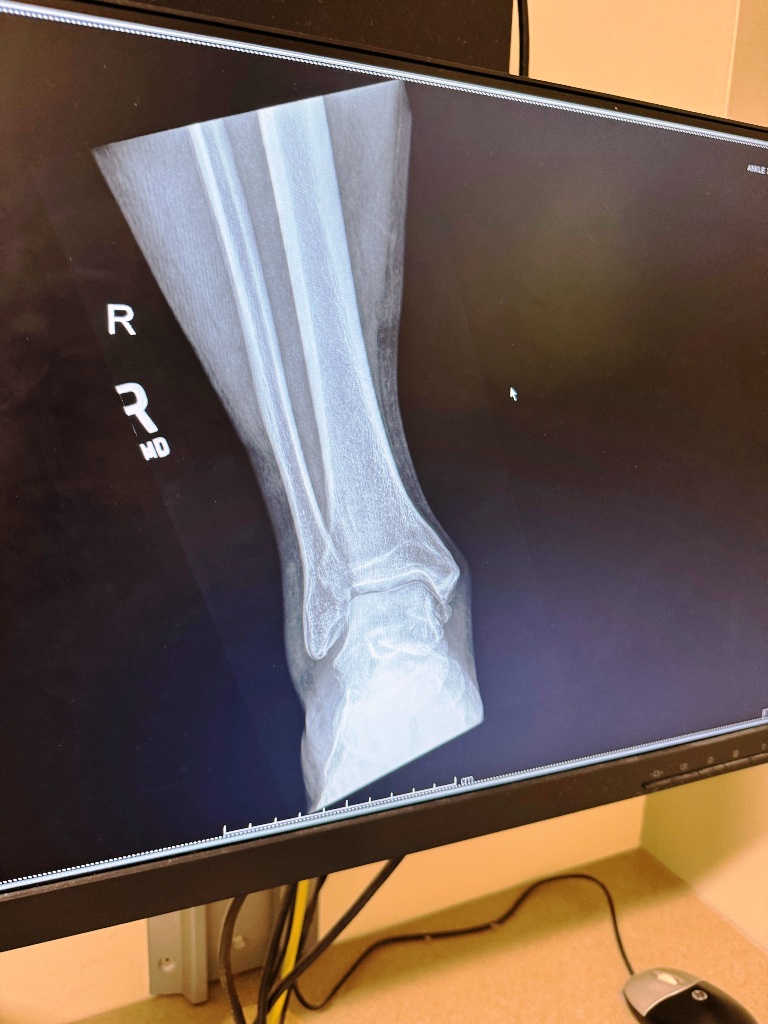

An X-ray told me that I had severe tenosynovitis in my foot, adjoining the sprain, and that there was a floating bone chip in my ankle from a previous fracture that doctors had missed. Also bone spurs. All of that explains the pain I’d been running through for last five years or so. The ensuing MRI confirmed that on top of the inflamed tendon sheath and bone problems, I also had two badly sprained ligaments running from the ankle up my leg.

The doctor said I might be done running, or at the very least, I was going to need to back off considerably. She said the tendon that holds that foot up is now lax. It doesn’t hold tension, and it can’t be fixed. So my foot will sag, and I will have to develop the muscles around the ankle to counter that, but I will be more and more prone to rolling it.

It’s nearly two months since the injury. I have another MRI coming up to determine whether there is any course of action that would improve my ankle more permanently than physical therapy alone or figure out the extent to which the joint is already arthritic. I don’t know what’s going to come of that.